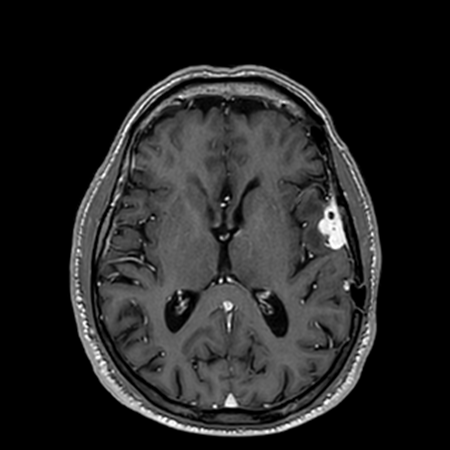

See the Difference

Compare the visual quality of our AI-enhanced images against traditional full-dose scans

AI-Enhanced

DeepGAD™ synthesized